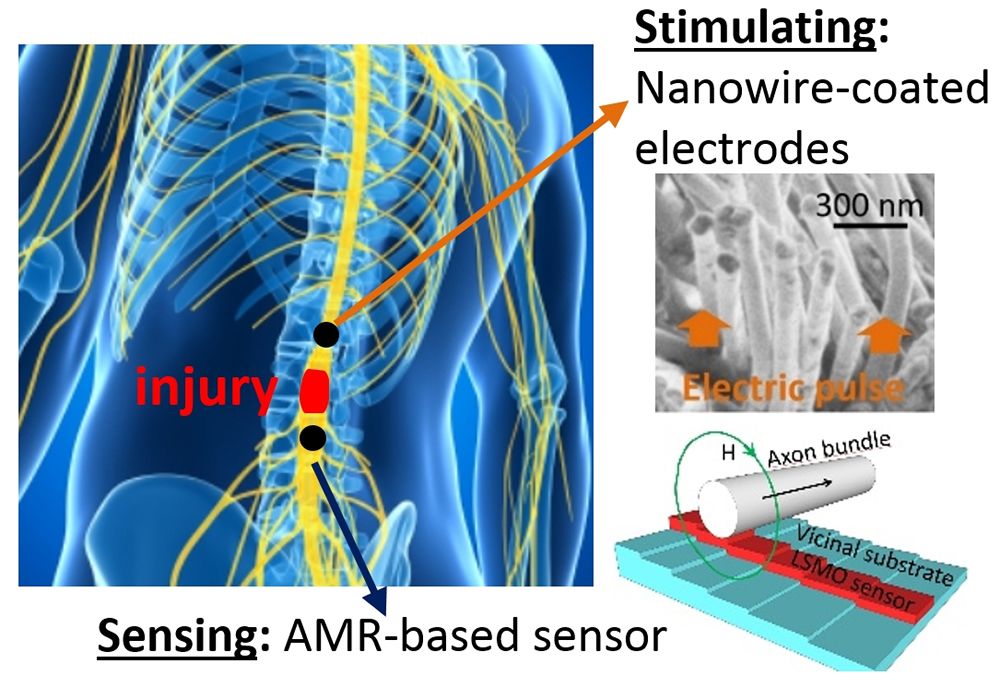

Para ser precisos ByAxon, cuya duración será de cuatro años a partir de enero de 2017, propone en último término "fabricar el prototipo de un implante activo que pueda funcionar directamente en la médula espinal lesionada, como un bypass. La función primordial de este dispositivo será restituir la trasmisión de señales neuronales sensoriales hasta el cerebro, actuando como un puente activo local en la médula espinal, algo que no es viable con la tecnología disponible la actualidad", comenta la doctora González.

Teresa González explica que en este proyecto "se emplearán materiales magneto resistivos de superficie escalonada a escala nanométrica para desarrollar sensores capaces de detectar el campo magnético producido por la actividad neuronal, cuyo valor es unas diez mil veces más pequeño que campo magnético terrestre". Para entender la especificidad de ByAxon, hay que destacar que un nanómetro es mil millonésima parte de un metro. La propia co-coordinadora de la investigación europea subraya que "detectar estas señales a nivel cerebral es tan sólo posible a día de hoy empleando la técnica de la magneto encefalografía, que requiere el uso de materiales superconductores, y por lo tanto de nitrógeno líquido para su funcionamiento.

En paralelo, los investigadores del proyecto fabricarán electrodos eléctricos de alta biocompatibilidad y adherencia gracias a su superficie cubierta de nanohilos conductores. Estos electrodos permitirán emitir impulsos eléctricos que desencadenen la actividad neuronal con bajo impacto, haciéndolos de gran interés también para tratamientos del párkinson o en implantes retinales. Así, el trabajo cubre tanto la detección como la producción de la actividad neuronal con una nueva generación de interfaces mejoradas de alta resolución y gran flexibilidad de uso.